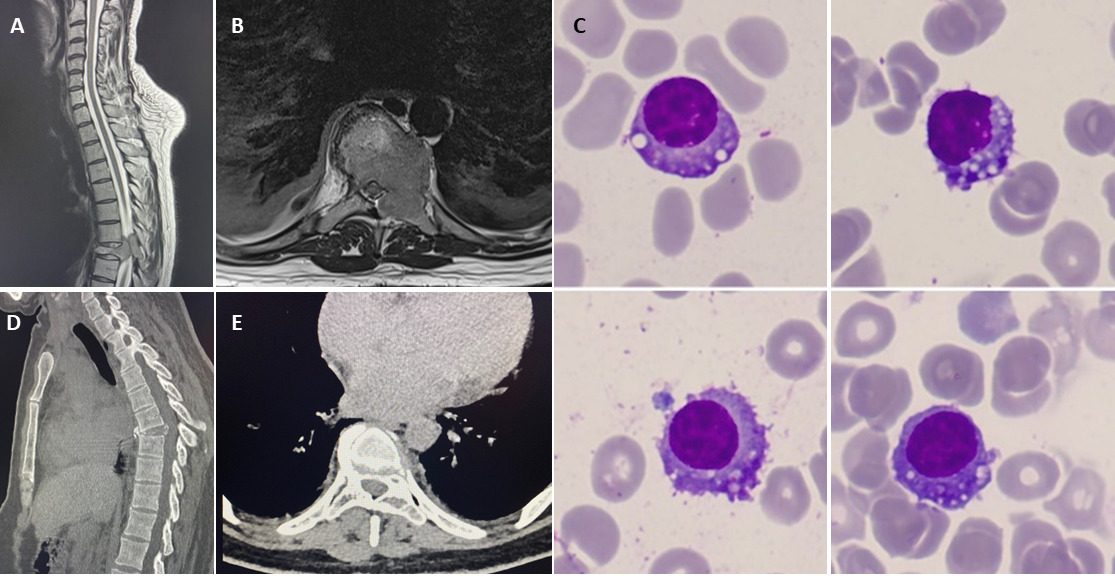

This patient presented with left sided thoracic pain which started during the first trimester of her third pregnancy. Pleuritic chest pain progressively worsened and she developed numbness of her right toes. A computed tomography pulmonary angiography (CTPA) in the third trimester ruled out a pulmonary embolus but identified collapse of thoracic (T) 8 vertebra. At 28 weeks, magnetic resonance imaging (MRI) of the whole spine confirmed collapse of the T8 vertebrae, with an epidural soft tissue component and signs of radiological cord compression (Figure 1). T8 soft tissue biopsy confirmed plasmacytoma. She was started on dexamethasone and transferred to our haematology ward at 29+6 weeks of gestation.

At presentation, at our centre, she had no neurological signs of MSCC. She underwent an urgent staging investigation. Whole body MRI showed large T8 lesion involving the body and left posterior elements with paramedullary involvement and cord compression. There was severe loss of vertebral height and a 14mm L5 lesion. Her MM workup showed Hb 108g/L, corrected calcium 2.50 mmol/L, creatinine 45 μmol/L, LDH 168 IU/L, albumin 39 g/L, β2-microglobulin 1.5 mg/L, lambda serum free light chain of 5612 mg/L, K/L ratio <0.01; IgG paraprotein was too small to quantify. Bone marrow aspiration and trephine (BMAT) showed 30-40% clonal plasma cells (Figure 1). Fluorescent in situ hybridisation (FISH) on CD138-selected cells showed loss of MAF only. She was diagnosed with MM, standard cytogenetics risk, ISS stage 1.

At 48-h postpartum, the patient underwent 20 Gy, 5 fraction radiotherapy to the T7-T9, which she tolerated well. Post-radiotherapy, she was allowed to mobilise wearing a thermoplastic thoraco-lumbar sacral orthosis (TLSO) brace, when upright, standing and walking.7 She was advised to avoid lifting, bending and twisting, and to sit at 45 degrees or lie down when the brace was removed. A week post-radiotherapy, she started systemic treatment with daratumumab, bortezomib, and dexamethasone. Thalidomide was added in cycle two with VTE prophylaxis when her mobility improved and the risk of VTE reduced. The patient made a full neurological recovery and has no residual neurological deficits or signs of spinal cord compression. Her baby was discharged from the NICU after four weeks in good health with adequate weight gain. After completion of four cycles of induction chemotherapy, the patient achieved very good partial response (normal serum free light chain (SFLC) level). Repeat spine MRI and CT four months later showed resolution of the T8 lesion and new bone formation (Figure 1). Six months following her presentation, she was weaned off the brace and underwent melphalan (200 mg/m2) ASCT.